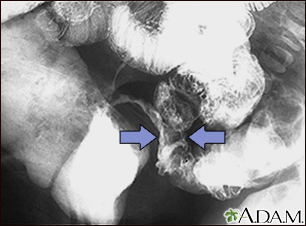

Crohn disease - X-rayBackCrohn disease - X-rayThis lower abdominal x-ray shows narrowing (stenosis) of the end of the small intestine (ileum), caused by Crohn disease. Crohn disease typically affects the small intestine, whereas ulcerative colitis typically affects the large intestine. A solution containing a dye (barium), was swallowed by the patient. When it passed into the small intestines, this x-ray was taken (lower GI series). E-mail FormEmail ResultsName:Email address:Recipients Name:Recipients address:Message: